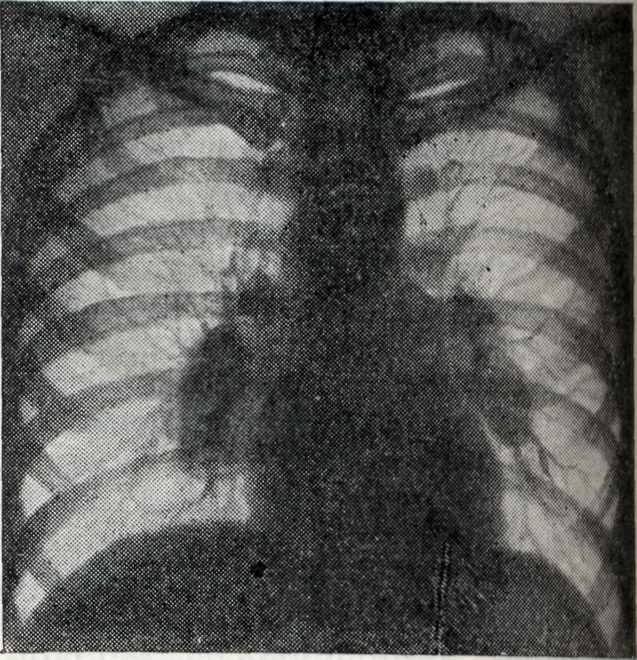

Рис. 2.

Правосторонний опухолевидный бронхаденит. Правый корень расширен, уплотнён, контуры его чёткие, полицикличные. Слева корень структурен, не расширен (рентгенограмма).

Проекции бронхов менее отчётливы, тень корня почти сливается с тенью средостения. Наружная волнообразная или бугристая граница деформированного корня проецируется в виде отчётливой, хотя и не всегда резкой линии, что зависит от отсутствия или наличия воспалительных изменений в капсуле лимф, узлов. При одностороннем опухолевидном Б. изменения корня противоположного лёгкого менее выражены (рис. 2), на стороне поражения лёгочный рисунок несколько усилен, прилежащие листки междолевой плевры уплотнены (рис. 3).